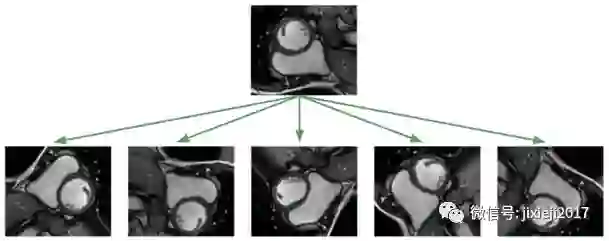

分割这些MRI对于未经专门训练的人来说是非常困难的:

利用深度学习方法解决这个问题,面临的最大挑战是数据集太小。数据集仅包含如上图所示的243张医师已分割的、来自有16例患者的MRI图像。另外还有3697个未标记图像,它们对于无监督或半监督学习可能有用的,但这个项目是一个监督学习的问题,我不考虑使用这些图像。图像大小为216×256像素。